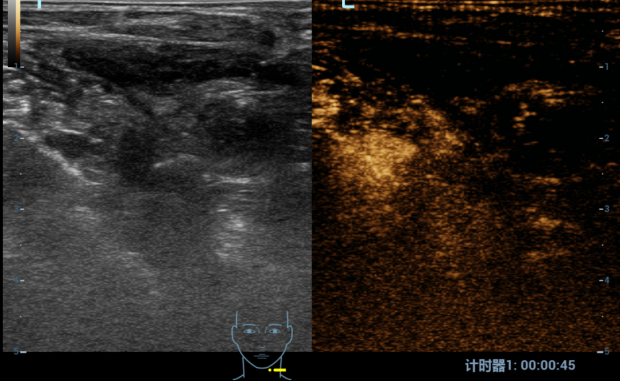

甲状旁腺结节术前细针穿刺

术前造影

结节明显强化